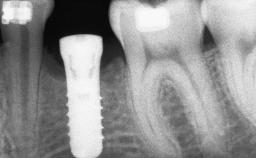

Guided Bone Regeneration (GBR) with a Particulated Autologous Graft and a ePTFE-Reinforced Membrane for Vertical Augmentation of a Single-Tooth Edentulous Space in the Esthetic Zone

| # of Teeth | 1 |

| # of Implants | 1 |

| Type of Implants | Two-Piece |

| Bone Level at Adjacent Teeth | <= 5 mm to contact point | 5.5 to 6.5 mm to contact point | > 7 mm to contact point |

| Bone Volume | Deficient vertically or deficient vertically AND horizontally |